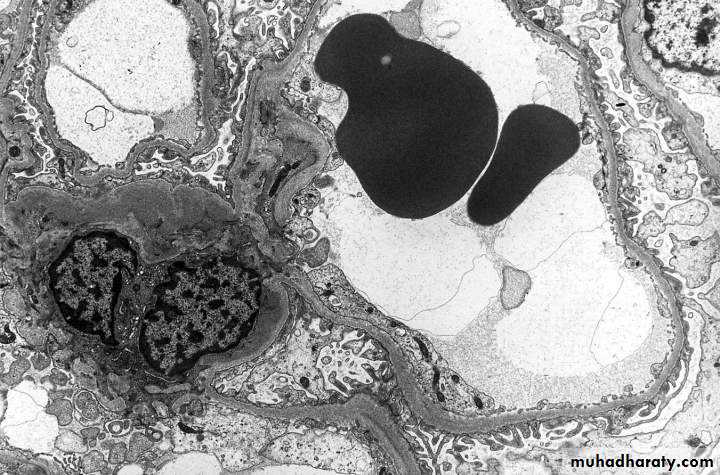

Electron microscopy shows distinct rupture in the basement membrane.

By electron microscopy, there are irregular dense deposits between the basement membrane and the epithelial cells, appearing as irregular spikes, which are best seen by silver stains as black in color .These spikes by time thicken to produce dome-like protrusions.